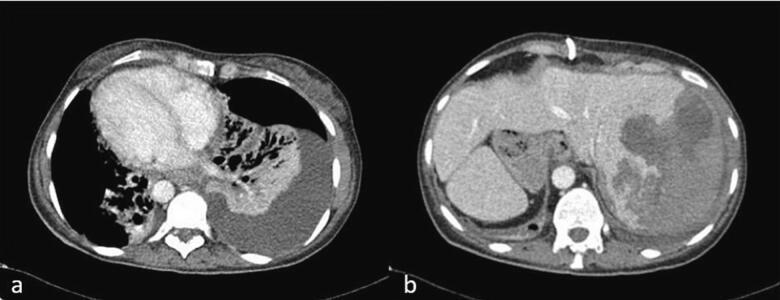

一名41岁的女性患者,已知患有卡塔格内综合征,因急性胆囊炎接受了腹腔镜胆囊切除术,并于术后第一天出院回家。然而,术后第五天,该患者因腹痛、发热和黄疸前往急诊室就诊。实验室检查显示白细胞增多和高胆红素血症。影像学检查显示CBD完全闭塞。选择了延迟治疗方法,在初次手术后六周进行了肝空肠吻合术。

腹腔镜胆囊切除术是胆囊疾病的标准手术方法。SIT独特的解剖结构增加了腹腔镜胆囊切除术期间CBD损伤的风险。外科医生需要进行镜像操作,并在SIT患者中遵循安全腹腔镜胆囊切除术的基本原则。这是SIT患者中第二例报告的CBD损伤病例。